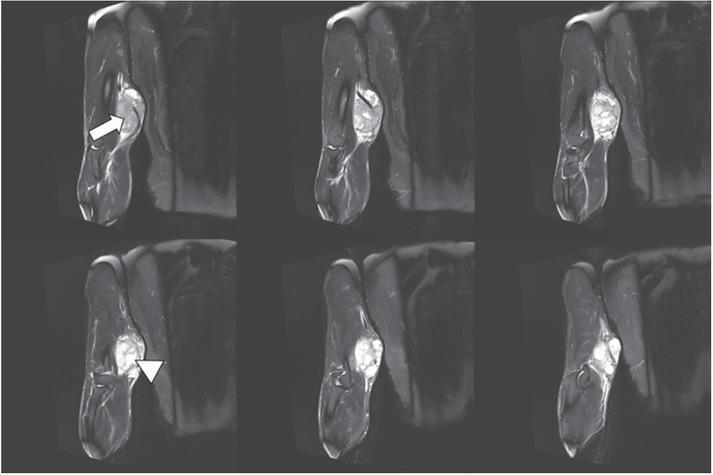

Figure 1